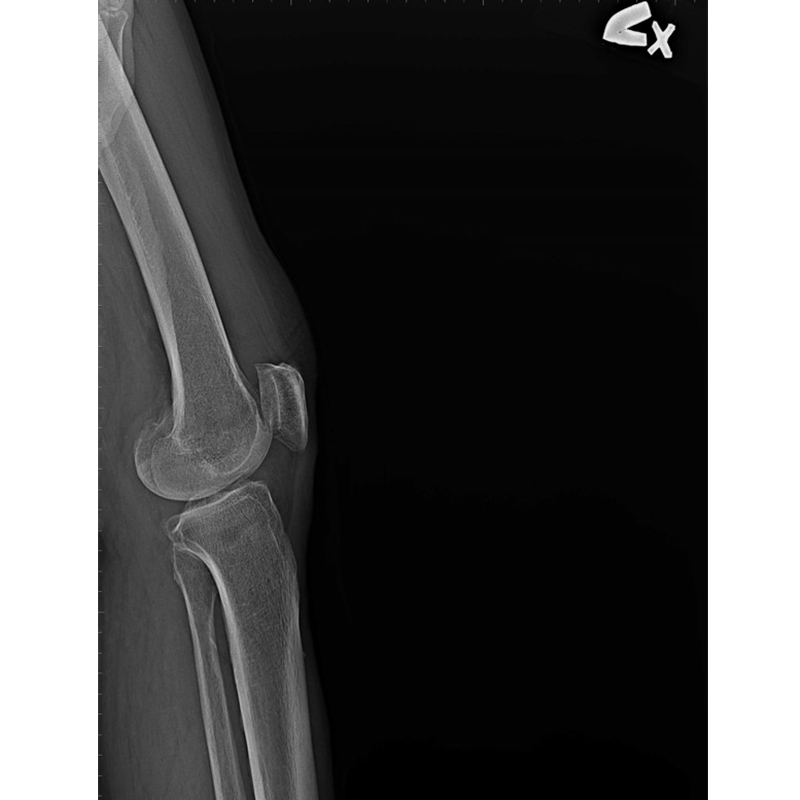

傳統部分膝置換 首頁 案例分享 膝關節手術 傳統部分膝置換 殷女士 65歲 術前 術後 張女士 71歲 術前 術後 蔡女士 74歲 術前 術後 張女士71歲 術前 術後 翁女士70歲 術前 術後 劉女士 80歲 術前 術後